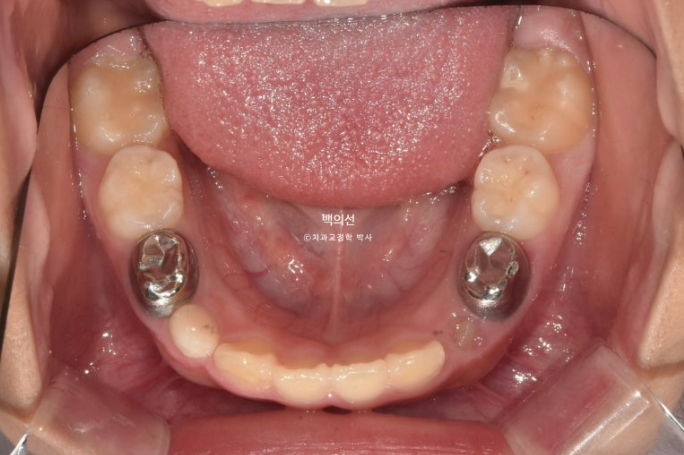

24년 8월까지, 9개월간 첫 세트의 30개 장치를 다 낀 후 모습입니다.

24.08

중심선은 잘 맞게 되었지만,앞니 교합이 절단교합입니다.

한쪽으로 틀어진 턱의 위치가 바로잡히는 과정에서 아래턱이 반대쪽으로 회전을 하면서 소량 앞으로 나오게 되기 때문입니다.

추가장치에서 이 부분은 개선해야 합니다.

영구치들이 올라올 공간은 적절하게 분배가 되었습니다.

새로 올라온 영구치들을 좀 더 배열하고 앞니 교합을 개선하기 위해서 추가장치를 제작합니다.

추가장치에서 아래턱의 위치를 잡아주는 기능은 넣지 않았으며 치료 후 MA 없이도 턱의위치가 안정적으로 유지되는 지를 확인하는 과정입니다.